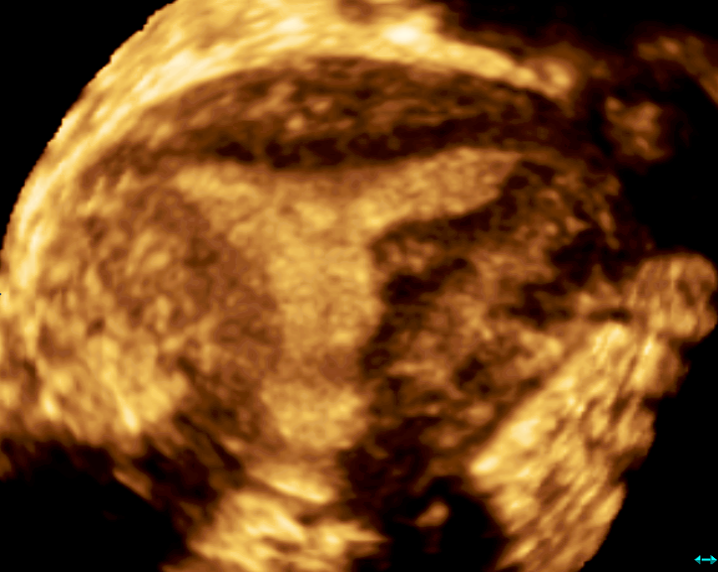

Современные экспертные УЗИ сканеры дают возможность проводить исследования всех органов в 3D. Это позволяет, используя полученный массив данных, получать диагностические сечения в любой плоскости, недоступной для обычного 2D УЗИ. Наиболее интересной является фронтальная. Например, визуализация полости матки. Диагностическая возможность выявления пороков развития превосходит все другие методы (рентгеновские и МРТ). Метод также позволяет уточнить положение ВМК (спирали) в полости матки, расположение миоматозных узлов, расположение плодного яйца на малых сроках, полипов. Сегодня современное экспертное ультразвуковое исследование невозможно без использования 3D УЗИ.